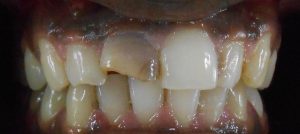

TREATMENTS

SERVICES

| 12 | Composite Laminates- Direct |

| 13 | Indirect Composite Restoration |

| 14 | Metal Crown |

| 15 | Porcelain Facing With Metal Backing |

| 16 | Full Ceramic Crown |

| 17 | Post And Core (Cast) |

| 18 | Fibre Post Core |

| 27 | Home Bleaching (Micro – Macro Abrasion) |

| 28 | Vital Bleaching (Zoom) |

| 29 | Vital/ Non Vital Office Bleach |